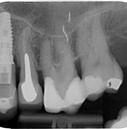

A posterior fogak direkt kompozit

restaurációinak

Vizuális klinikai esetismertetés

A posterior fogak direkt kompozit restaurációja az egyik leggyakrabban végzett beavatkozás a fogá-

szatban. Az elmúlt években kiemelt figyelem irányult az elérhető eredmények optimalizálására, különös tekintettel a II. osztályú kavitás dobozának (Class II box) kialakítására,

finírozása és polírozása

és a polimerizációs zsugorodásból eredő feszültség kezelésére. A téma körüli széles körű szakmai diskurzus ellenére van egy olyan lépés, amely gyakran nem kapja meg a kellő fi-

gyelmet: a mechanikai formázás protokollja. A mechanikai formázás alatt a restauráció kontúrjának kialakítását, a felesleges kompozit eltávolítását értjük a marginális szélekről, illetve ide tartozik a végső polírozás is. Ez a folyamat három fő lépésre bontható: a felszín oxigén által gátolt, nem polimerizált rétegének eltávolítása, a durva finírozás és a végső polírozás. Jelen publikációban részletesen bemutatjuk ezeket a lépéseket, valamint egy klinikailag hatékony megközelítést vázolunk fel a direkt posterior kompozit restaurációk befejezésére.

1. ábra: A restauráció peremének polírozása.

2. ábra: A páciens egy nem megfelelő I. osztályú ezüst-amalgám töméssel és II. osztályú szuvasodással jelentkezett. A fog izolálása kofferdám alkalmazásával történt.

3. ábra: A preparálás, a bondozás és a kompozit felvitele után. (Megjegyzés: némi kompozit túlfolyás látható a mesiális doboz axiális falain).

4. ábra: A durva finírozás után a restauráció pereme sima és anatómiailag is megfelelő.

Klinikai példa az 2–4. képeken látható.